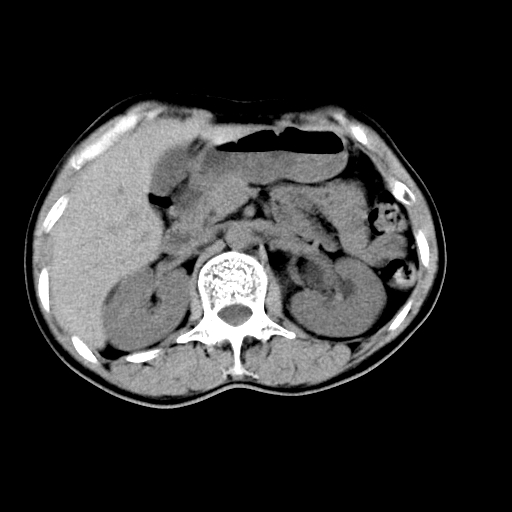

男,47岁,左输尿管结石碎石治疗后10余日。彩超示:左输尿管下段狭窄、输尿管积水。请各位讨论一下左输尿管下段结石还是静脉石?

两侧髂总动脉壁斑状及点状钙化.左侧输尿管行经与左髂总动脉相交后见高密度影,且下段输尿管管腔未见扩张,应该要考虑结石伴以上输尿管及肾盂积水.但右侧结节状高密度影,也应该是结石吧!那以上输尿管未见扩张呢!因此静脉结石可能性也较大.请问楼主碎石前左侧输尿管结石位置.

建议:把输尿管、膀胱扫全,除外输尿管下端结石,必要时强化或泌尿系造影除外其他.

左侧输尿管有轻度扩张伴有肾盂积水,输尿管下段周围的高密度影不象在输尿管内。

我认为不是结石的可能性大,因为他的位置和血管钙化的位置邻近